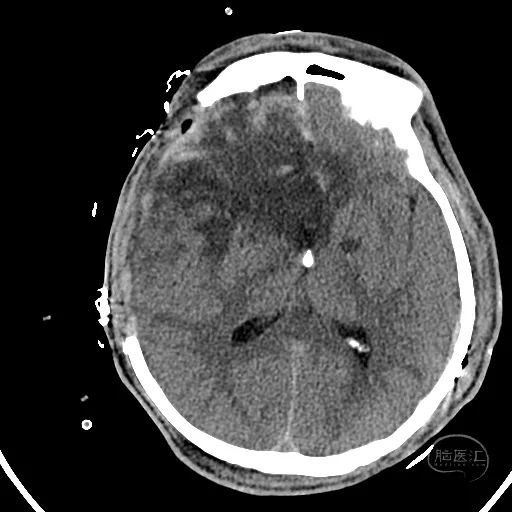

2小时后复查颅脑CT显示第四脑室受压消失。

小脑挫伤灶水肿较前加重,脑干及小脑半球低密度改变。

硬膜外血肿无明显变化。

右额叶脑挫裂伤并脑内血肿形成,中线结构明显移位。

左侧脑室有扩张表现。

此时患者双侧瞳孔散大,GCS评分4分,气管插管,自主呼吸。家属同意手术治疗。

幕上脑疝,幕下压力也高,第四脑室闭塞,导水管显示不清,脑室有扩张表现。